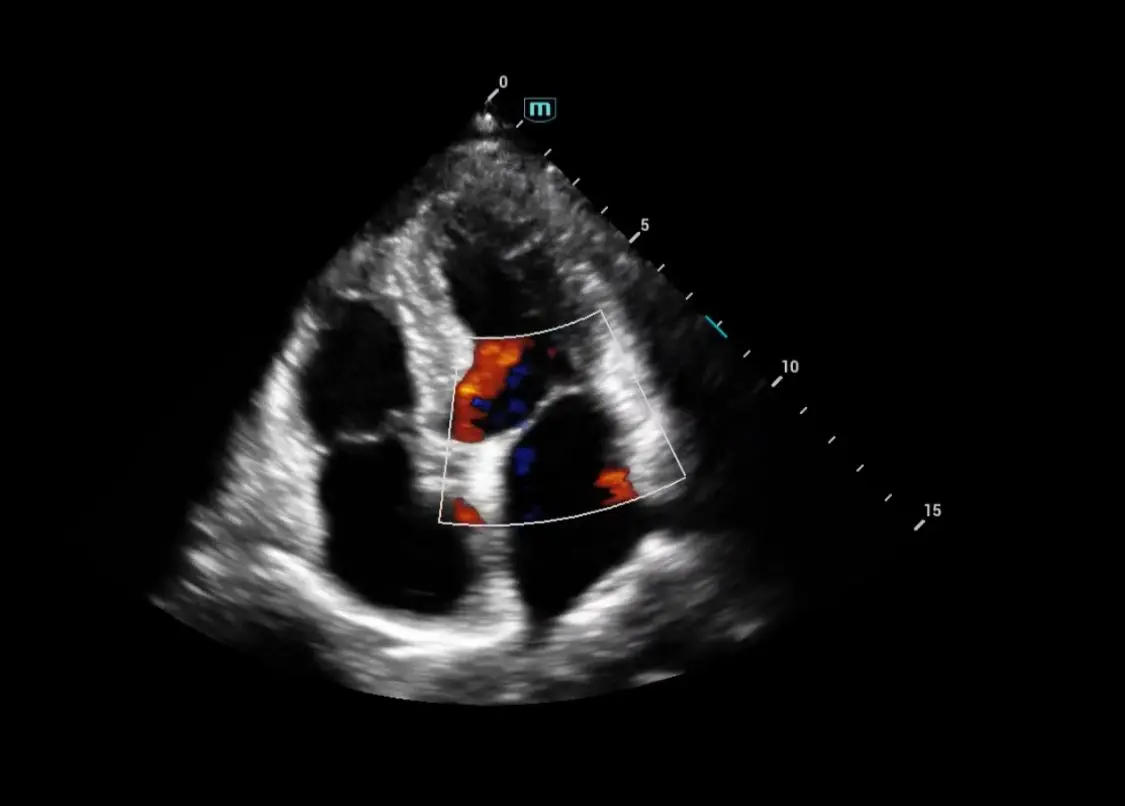

Ecocardiograma Doppler Color Transtorácico y Strain Longitudinal

Incluye perfil de lípidos 11 elementos.

Evalúa cavidades, válvulas, flujo y fuerza de contracción. Dirigido a pacientes con presión alta, dolor torácico, arritmias o revisión preventiva.

¿Qué es el Ecocardiograma ?

El ecocardiograma es un estudio de imagen cardíaca que utiliza ultrasonido para obtener imágenes en tiempo real del corazón. Es una de las principales herramientas diagnósticas en cardiología porque no es invasivo, determina cardiopatías, insuficiencia cardiaca , el flujo sanguíneo , enmerdades valvulares.

¿Qué es el Ecocardiograma Doppler con Strain?

Es una evaluación cardiovascular de alta precisión que permite analizar el funcionamiento estructural y mecánico del corazón en tiempo real, midiendo no solo la anatomía, sino también la contractilidad y deformación miocárdica (Strain). Con la tecnología Philips Affinity 70, LIB Laboratorios ofrece un estudio de nivel hospitalario, ideal para la detección temprana de enfermedades cardíacas (insuficiencia, Valvulopatías, Fibrosis, Isquemias, Amiloidosis…) y el seguimiento de tratamientos farmacológicos (Cardiotoxicidad).